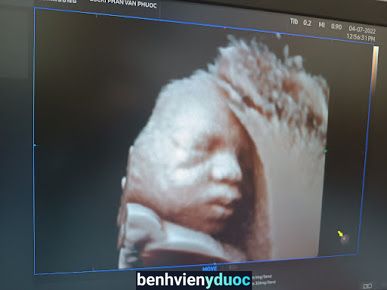

Phòng khám siêu âm 5D - BSCKI Phan Văn Phước là một phòng khám với nhiều kinh nghiệm và chuyên môn sâu rộng trong lĩnh vực y tế tại địa bàn Huyện Phù Cát, Tỉnh Bình Định.

Với một đội ngũ y tế chuyên nghiệp và nhiệt tình, Phòng khám siêu âm 5D - BSCKI Phan Văn Phước cam kết mang lại một trải nghiệm y tế tốt nhất cho mọi bệnh nhân.Phòng khám được đánh giá 5 sao trên tổng số 20 đánh giá.